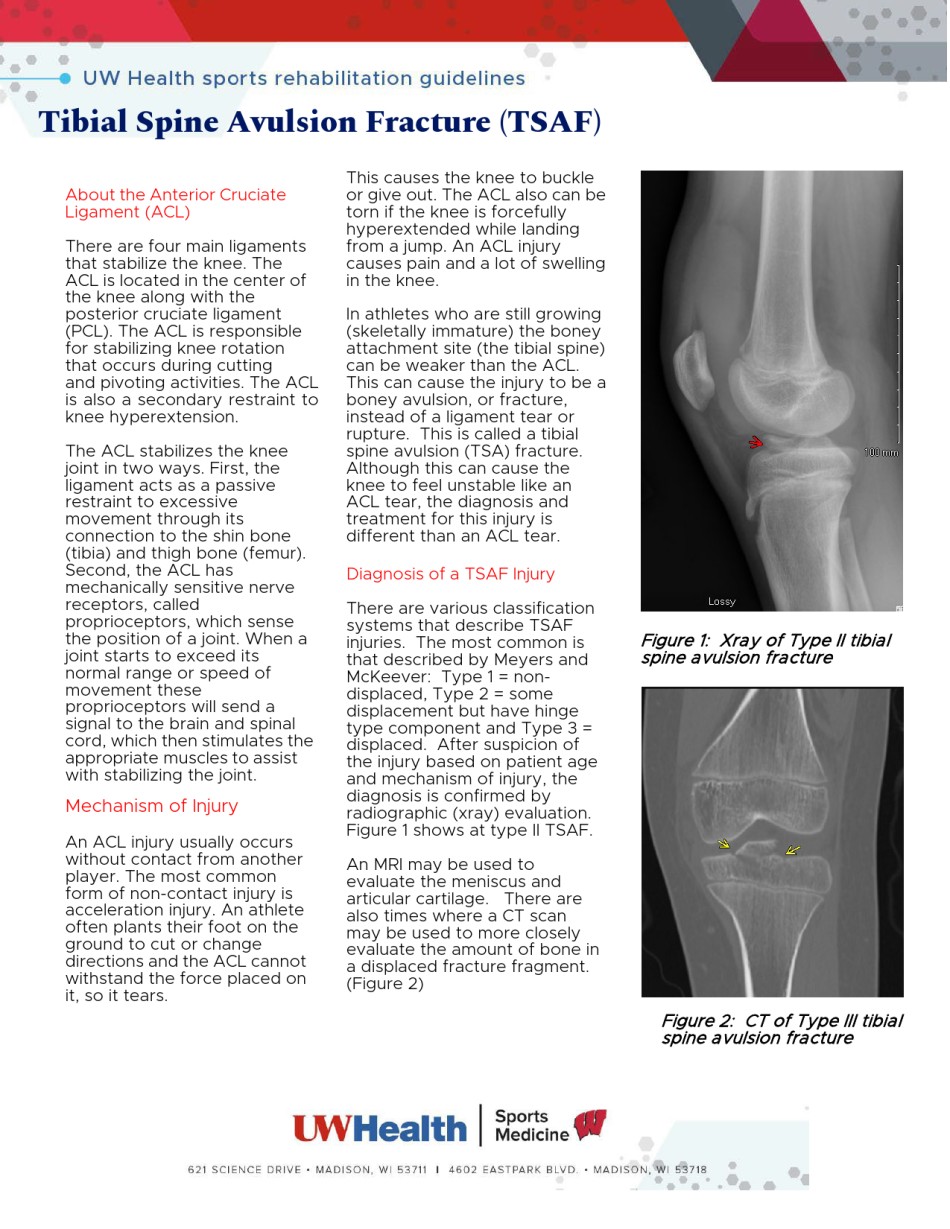

TibialSpineAvulsionFracture(TSAF)AbouttheAnteriorCruciateThiscausesthekneetobuckleFigure1:XrayofTypeIItibialLigament(ACL)orgiveout.TheACLalsocanbespineavulsionfracturetornifthekneeisforcefullyTherearefourmainligamentshyperextendedwhilelandingFigure2:CTofTypeIIItibialthatstabilizetheknee.Thefromajump.AnACLinjuryspineavulsionfractureACLislocatedinthecenterofcausespainandalotofswellingthekneealongwiththeintheknee.posteriorcruciateligament(PCL).TheACLisresponsibleInathleteswhoarestillgrowingforstabilizingkneerotation(skeletallyimmature)theboneythatoccursduringcuttingattachmentsite(thetibialspine)andpivotingactivities.TheACLcanbeweakerthantheACL.isalsoaseconda...